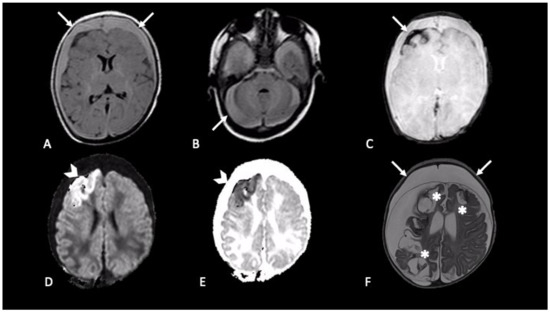

2.1. Hemorrhages

2.2. Parenchymal Injury